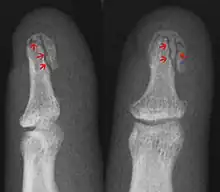

- Avulsion fracture – a fracture where a fragment of bone is separated from the main mass

| Avulsion fracture | A fragment of bone is separated from the main mass (image shows a Busch fracture) | |||